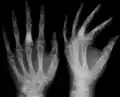

The disease consists of the growth multiple enchondromas which usually develop in early childhood. The growth of these enchondromas usually stops after skeletal maturation.[4] The affected extremity is shortened (asymmetric dwarfism) and sometimes bowed due to epiphyseal fusion anomalies. Bone lesions generally present as cellular during childhood and become more solitary over time. People with Ollier disease are prone to breaking bones (fractures) and normally have swollen, aching limbs. However, many cases of solitary enchondromata go unnoticed due to lack of symptoms. Enchondromas are commonly found in the phalanges, metacarpal, and metatarsal bones in patients of Ollier disease due to the affinity of enchondromas to long tubular bones such as the femur and humerus. A unilateral distribution of bone lesions is usually observed but bilateral distributions or a singular extremity can occur as well. Approximately a third of the cases show some form of physical deformities of bowing or abnormal limb lengthening.

Corticoplasty has been shown to have success in treating hand lesions and deformities while retaining normal function.[23][24] The surgery utilizes the removal of tissue (curettage) and bone reconstruction in order to remove enchondromas and improve cosmetic appearance. Many cases of corticoplasty have been shown improvement in appearances while maintaining function. Recurrence of enchondromas was observed in some cases. In cases of Ollier disease, early surgical treatment of enchondromas in the hand is recommended.